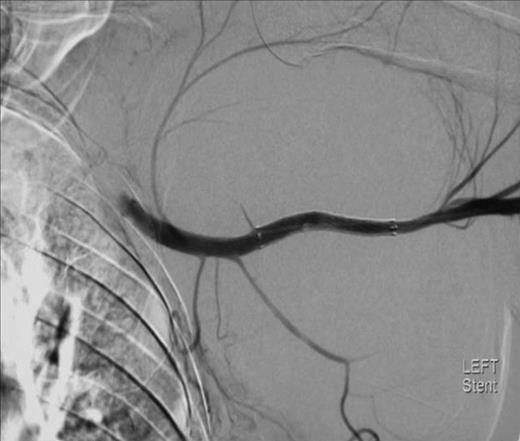

To attempt endovascular repair, an operative approach to the brachial artery preceded retrograde insertion of a 6cm long, 8mm thick Fluency nitinol self-expanding PTFE covered stent (Bard). This excluded the lesion successfully (figures 4 and 5). The haematoma was decompressed. Aspirin 75mg and clopidogrel 75mg were initiated for stent protection. The patient suffered a postoperative axillary wound infection which was treated successfully with antibiotics. There had been no recovery of neurological function in the arm. Neurophysiological studies revealed a proximal axonotmesis with a poor prognosis.

The lesion was repaired by an endovascular retrograde approach whereby the neck of the lesion was located just distal to the origin of the subscapular artery and the cavity excluded successfully by the insertion of self-expanding Fluency nitinol PTFE-covered stent (Bard). Such a method was favoured here because the condition of the arm rendered open approaches hazardous. There are several reports of the treatment of such lesions by stent graft, including those of Xenos (10), whilst open repair also offers a simultaneous opportunity to explore for and deal with associated injuries.